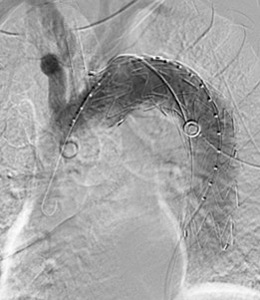

- Type II endoleak (A);

- Celiac branches temporary robotic clamping (B);

- Check with indocyanin green injection (C);

- Type II endoleak complete resolution after celiac trunk ligature (D).